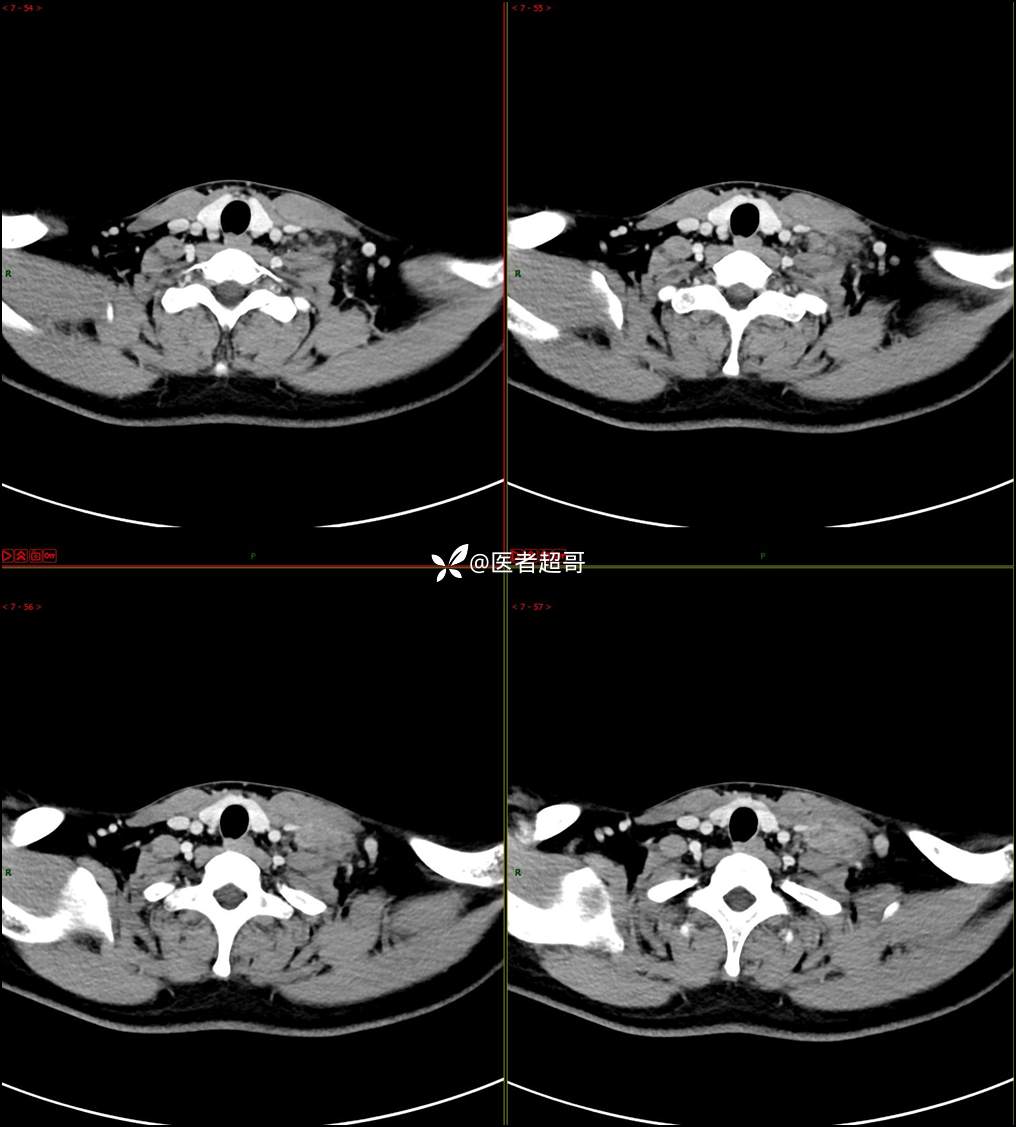

现病史:患者自述10余天前无意中发现左侧颈部一肿物,颈部活动时、进食时伴疼痛,无发热,患者前往人民医院就诊,给予输液治疗(头孢呋辛钠2g bid 硫酸阿米卡星0.4g qd、)10天,患者感肿物轻微变小,后患者为求进一步治疗,昨日来我院门诊就诊,给予颈部彩超示:左颈部实性肿物,神经来源?,左颈部肿大淋巴结;颈部ct平扫+强化示:左侧锁骨上区占位,神经鞘瘤?双侧颈部多发淋巴结;门诊以“局部肿物”收治入院,患者自患病以来,神志清,精神可,饮食睡眠可,体重无明显变化,二便正常。